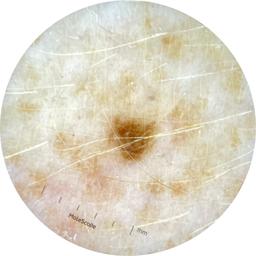

ISIC_9785574

2003 x 2003

Field Value

acquisition_day 148

age_approx 45

anatom_site_1 Head and neck

anatom_site_general head/neck

concomitant_biopsy False

diagnosis_1 Benign

diagnosis_confirm_type single image expert consensus

family_hx_mm True

image_manipulation instrument only

image_type dermoscopic

lesion_id IL_0236417

patient_id IP_8456088

personal_hx_mm True

sex female